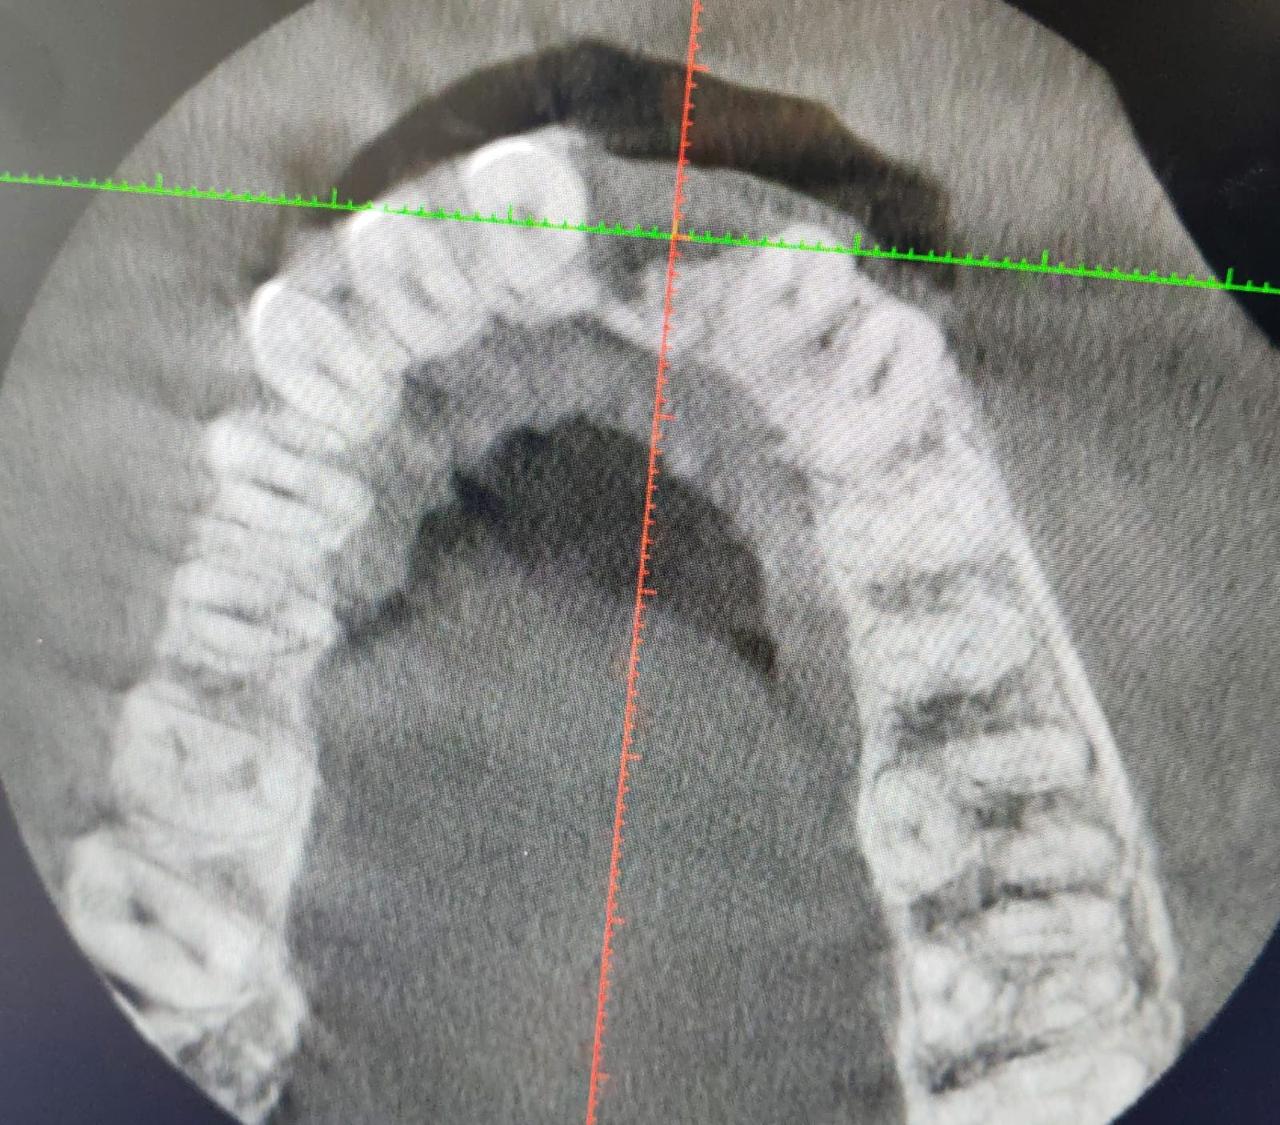

Dr Matshidiso Mphahlele-Ntladi is an accomplished dental professional whose extensive qualifications and experience underscore her commitment to excellence in oral health care. With a robust educational background, she holds a Diploma in Oral Hygiene, a Bachelor’s Degree in Dental Therapy, a Bachelor’s Degree in Dentistry, and a Postgraduate Diploma in Aesthetic Dentistry. Additionally, she possesses a Dispensing License and is currently pursuing a Postgraduate Diploma in Implantology, demonstrating her dedication to continuous learning and staying at the forefront of dental innovations.

Furthermore, her ongoing pursuit of advanced education in implantology reflects her ambition and commitment to professional growth. Dr. Mphahlele-Ntladi is not only a skilled clinician but also a lifelong learner, always seeking to expand her knowledge and enhance her practice.